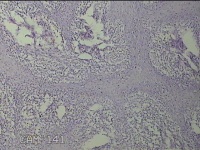

左拇指结节

性别

男

年龄

42岁

临床诊断

皮下结节

一般病史

发现左拇指结节8年余。

标本名称

大体所见

灰白粉红色组织1.3x0.8x0.3cm一块,表面带梭形皮肤1.3x1.1cm,皮下见结节0.8x0.5cm一个,切开结节呈实性,切面灰白粉红色,质中。

良性病变。